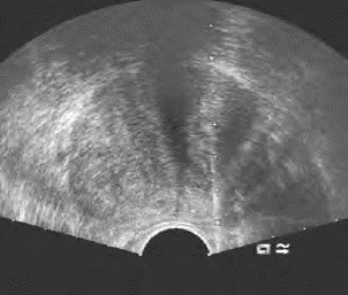

3.经直肠介入性超声可开展的内容 疑似前列腺肿瘤穿刺活检(图3-3)、前列腺癌放射性粒子置入、盆腔肿瘤穿刺活检,精囊腺囊肿硬化治疗等。

图3-3 经直肠超声引导下前列腺穿刺活检声像图